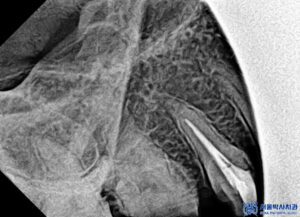

또한 정밀한 확인을 위해

3D CT를 촬영하였습니다.

위쪽 치아 뿌리 끝 염증을

확인할 수 있었습니다.

먼저 충치를 제거하였습니다.

충치가 비교적 깊은 위치까지

진행되어 있었으며,

그 영향으로 치아 뿌리 끝까지

염증이 퍼진 상태로 확인되었습니다.